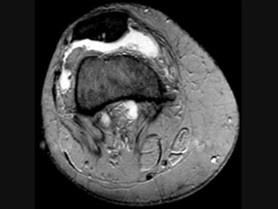

髌骨软骨软化症(如图)的治疗原则哪项是错误的 ( )A、非甾体类抗炎药B、一旦发现尽可能早手术治疗C、物理治疗D、关节内封闭 ...

问题 髌骨软骨软化症(如图)的治疗原则哪项是错误的 ( )

选项 A、非甾体类抗炎药 B、一旦发现尽可能早手术治疗 C、物理治疗 D、关节内封闭 E、股四头肌锻炼

答案 B